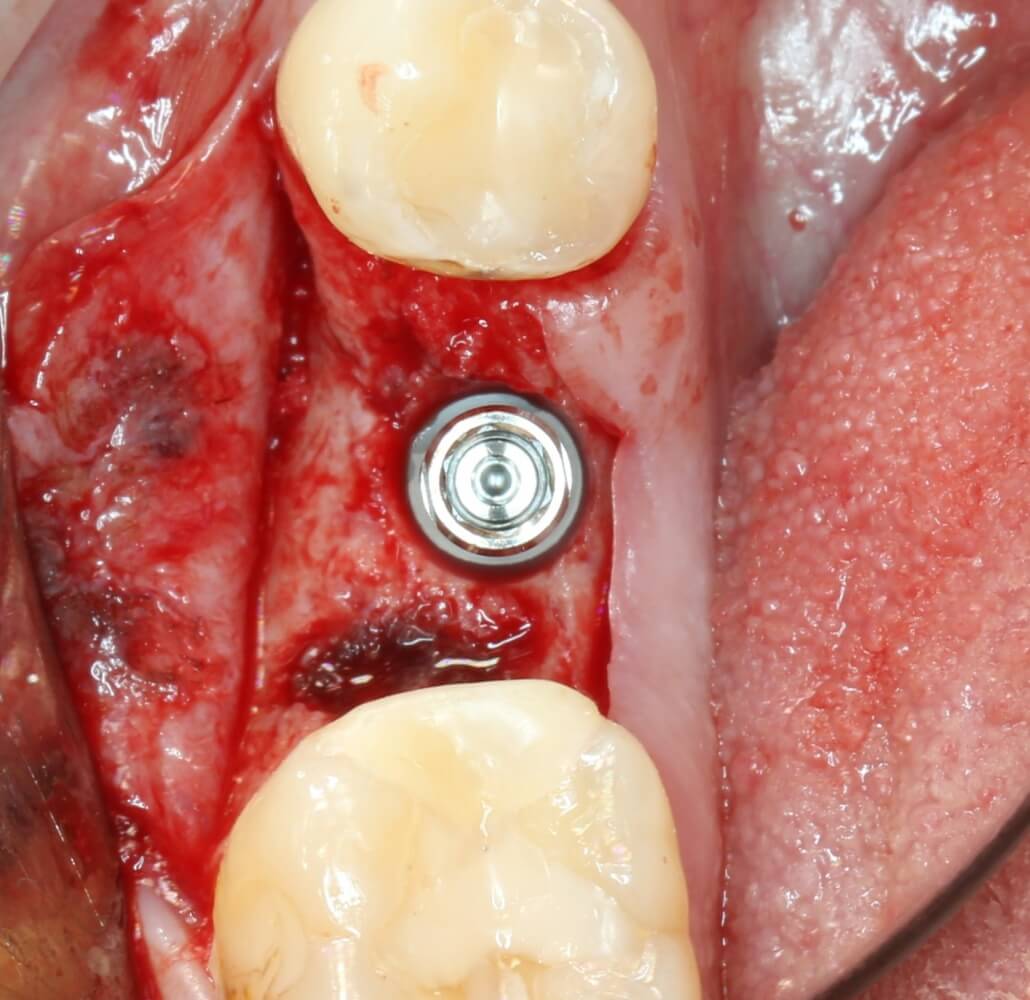

Рекомендации по установке имплантов. Для всех. Часть V.